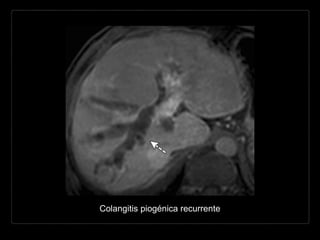

Colangitis piogénica recurrente

Hallazgos por RM

• T1: dilatación biliar hipointensa + cálculos de

intensidad intermedia (anillo hiperintenso)

• T2: bilis hiperintensa con cálculos hipointensos

• T1 + C: dilatación biliar hipointensa + cálculos de

• CPRM: dilatación intra- y extrahepática con

defectos de llenado representando cálculos.